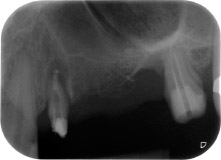

След един месец, в деня на операцията, болката и възпалението в зъб 24 е минимално, но подвижността в Miller class 2 е на лице. След отваряне на ламбата и почистването на периапикалната и перирадикуларната тъкани, обхватът на костния дефект стана очевиден (Фиг. 2 и 3).

В букалния корен, цялата вестибуларна и дистална кост липсва. Захващането е значително ограничено до палатиналния корен, подчертавайки предварително лошата прогноза. Зъб 27 също откри намалено хоризонтално захващане и минимално апикално разреждане (Фиг. 1) без клинични симптоми.